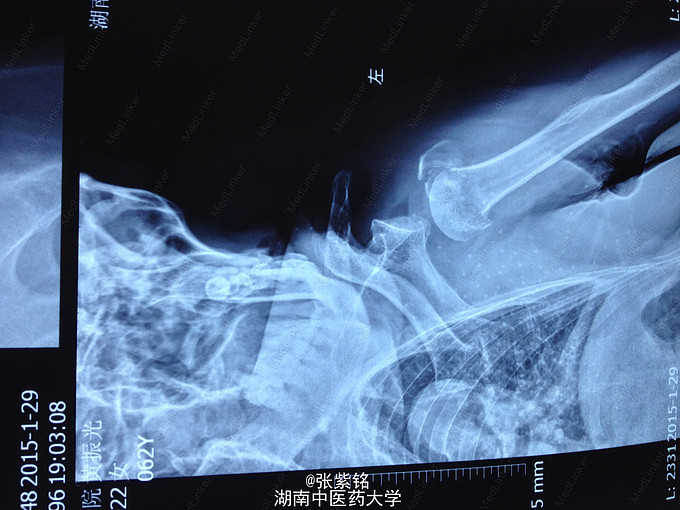

主诉:摔伤致左肩部肿痛,活动受限;头部疼痛伴活动性出血2小时余。 病史:在家中摔倒致伤左肩部、腰部及头部。症见:左肩关节及腰部肿痛,活动受限,精神一般,神志清,无畏寒、发热、头晕及呕吐等症状,二便正常。

查体见:左额部可见约2cm*2cm皮下血肿,并可见一不规则伤口约2cm,伴活动性出血。脊柱驼背畸形,胸椎后凸,头部前伸体态;颈、腰部旋转活动不能,腰部于L3-5椎体棘突处压痛明显,双下肢肌力、肌张力正常。左肩部关节明显肿胀,可扪及空虚感;局部压痛明显,左Dugas征阳性,左肩关节主动上举,外展,后伸,内收活动受限;被动活动患处疼痛加剧,左侧桡动脉搏动可扪及,皮肤感觉正常,左肘、腕及各指间关节血运感觉活动正常。 X线片示:左肩关节脱位,左肱骨外科颈骨折,左肱骨大结节撕脱性骨折。